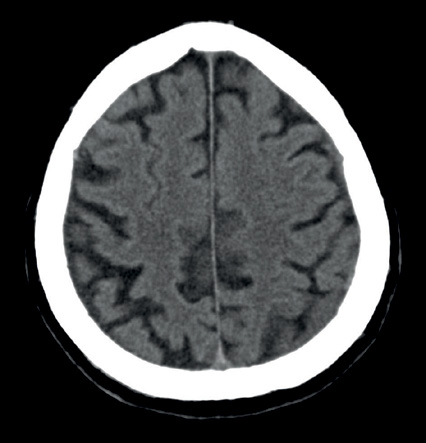

Image

Darstellung der Handwurzelknochen